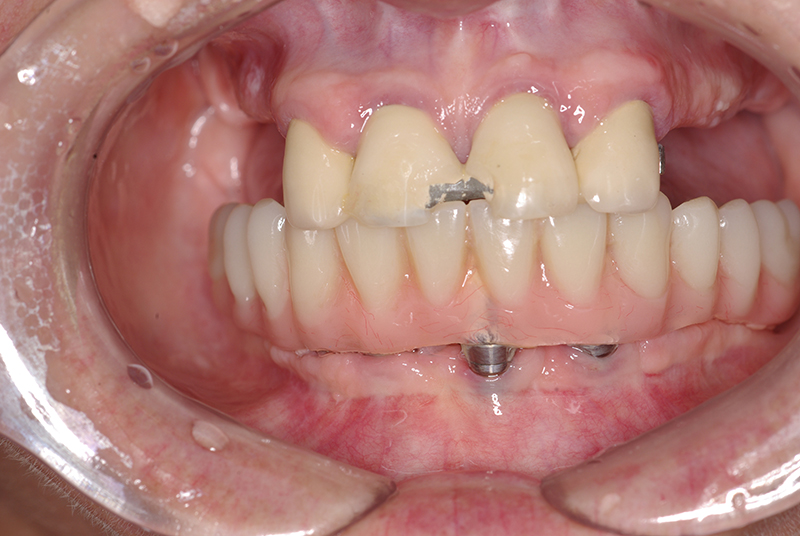

A Carga Imediata é uma técnica odontológica avançada que permite a colocação de uma prótese dentária fixa logo após a cirurgia de instalação dos implantes ou em poucos dias. Isso elimina a espera tradicional de meses para a integração completa do implante ao osso, oferecendo uma solução rápida e segura para restaurar dentes perdidos.

- Cirurgia de Instalação dos Implantes: Os implantes são fixados no osso maxilar ou mandibular, proporcionando uma base sólida para a prótese.

- Fixação da Prótese: Em até 72 horas após a cirurgia, a prótese provisória é instalada, permitindo que o paciente recupere a funcionalidade e a estética imediatamente.